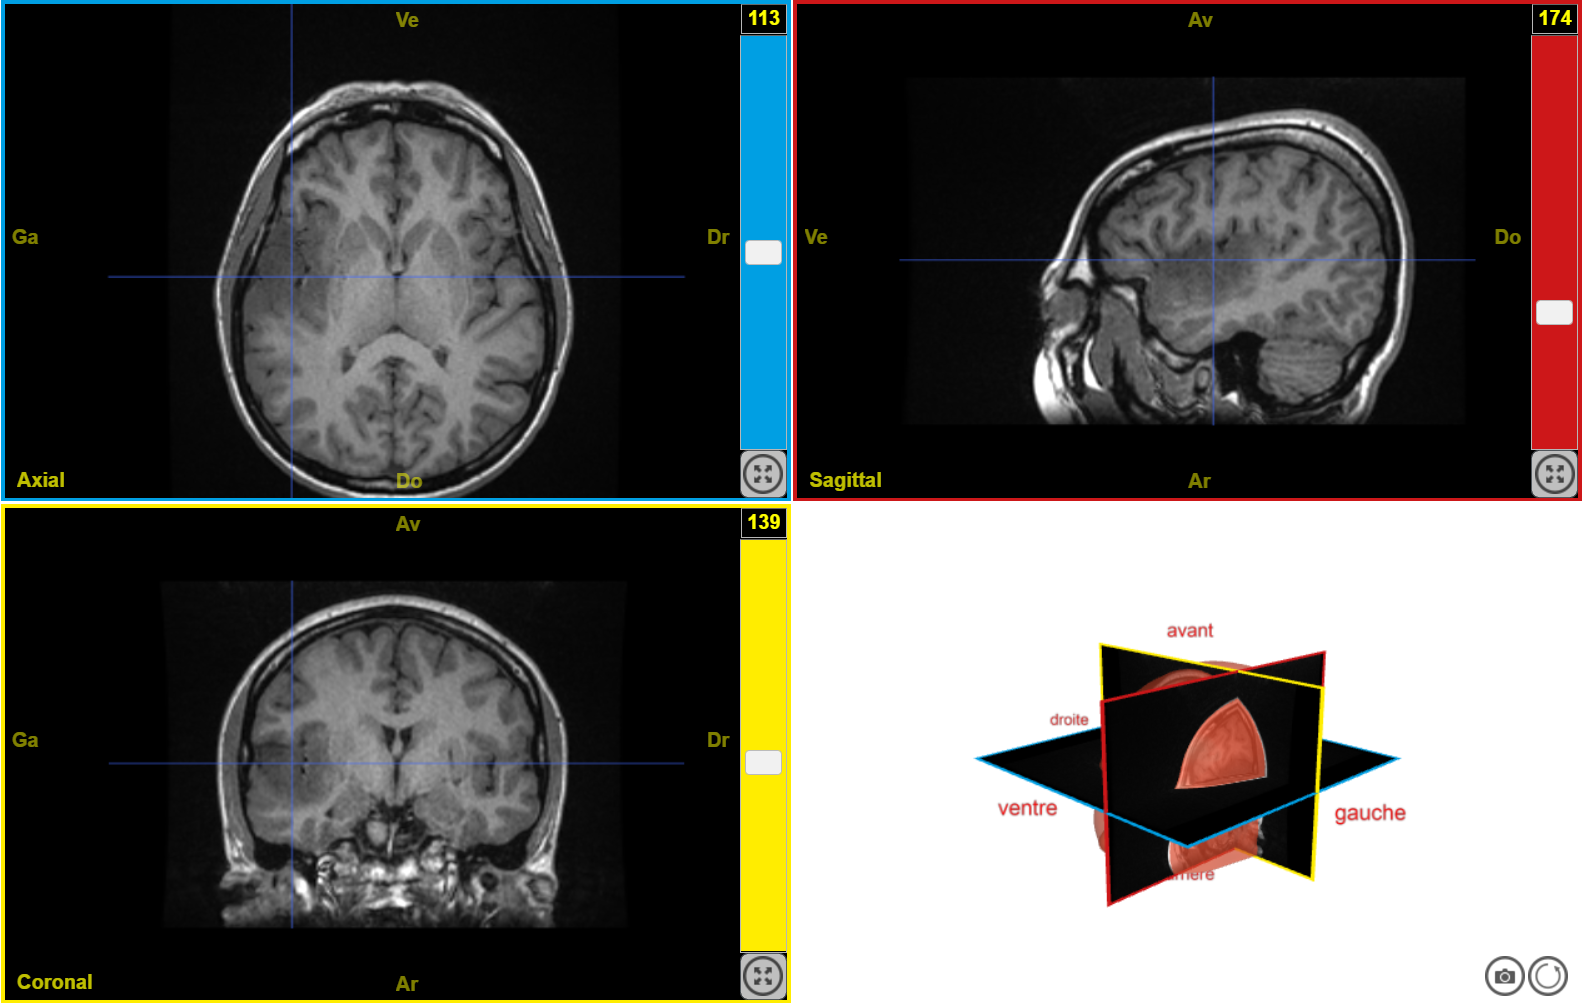

IRM tumeur T1 n1

Image dans sa taille originale :

501 ko